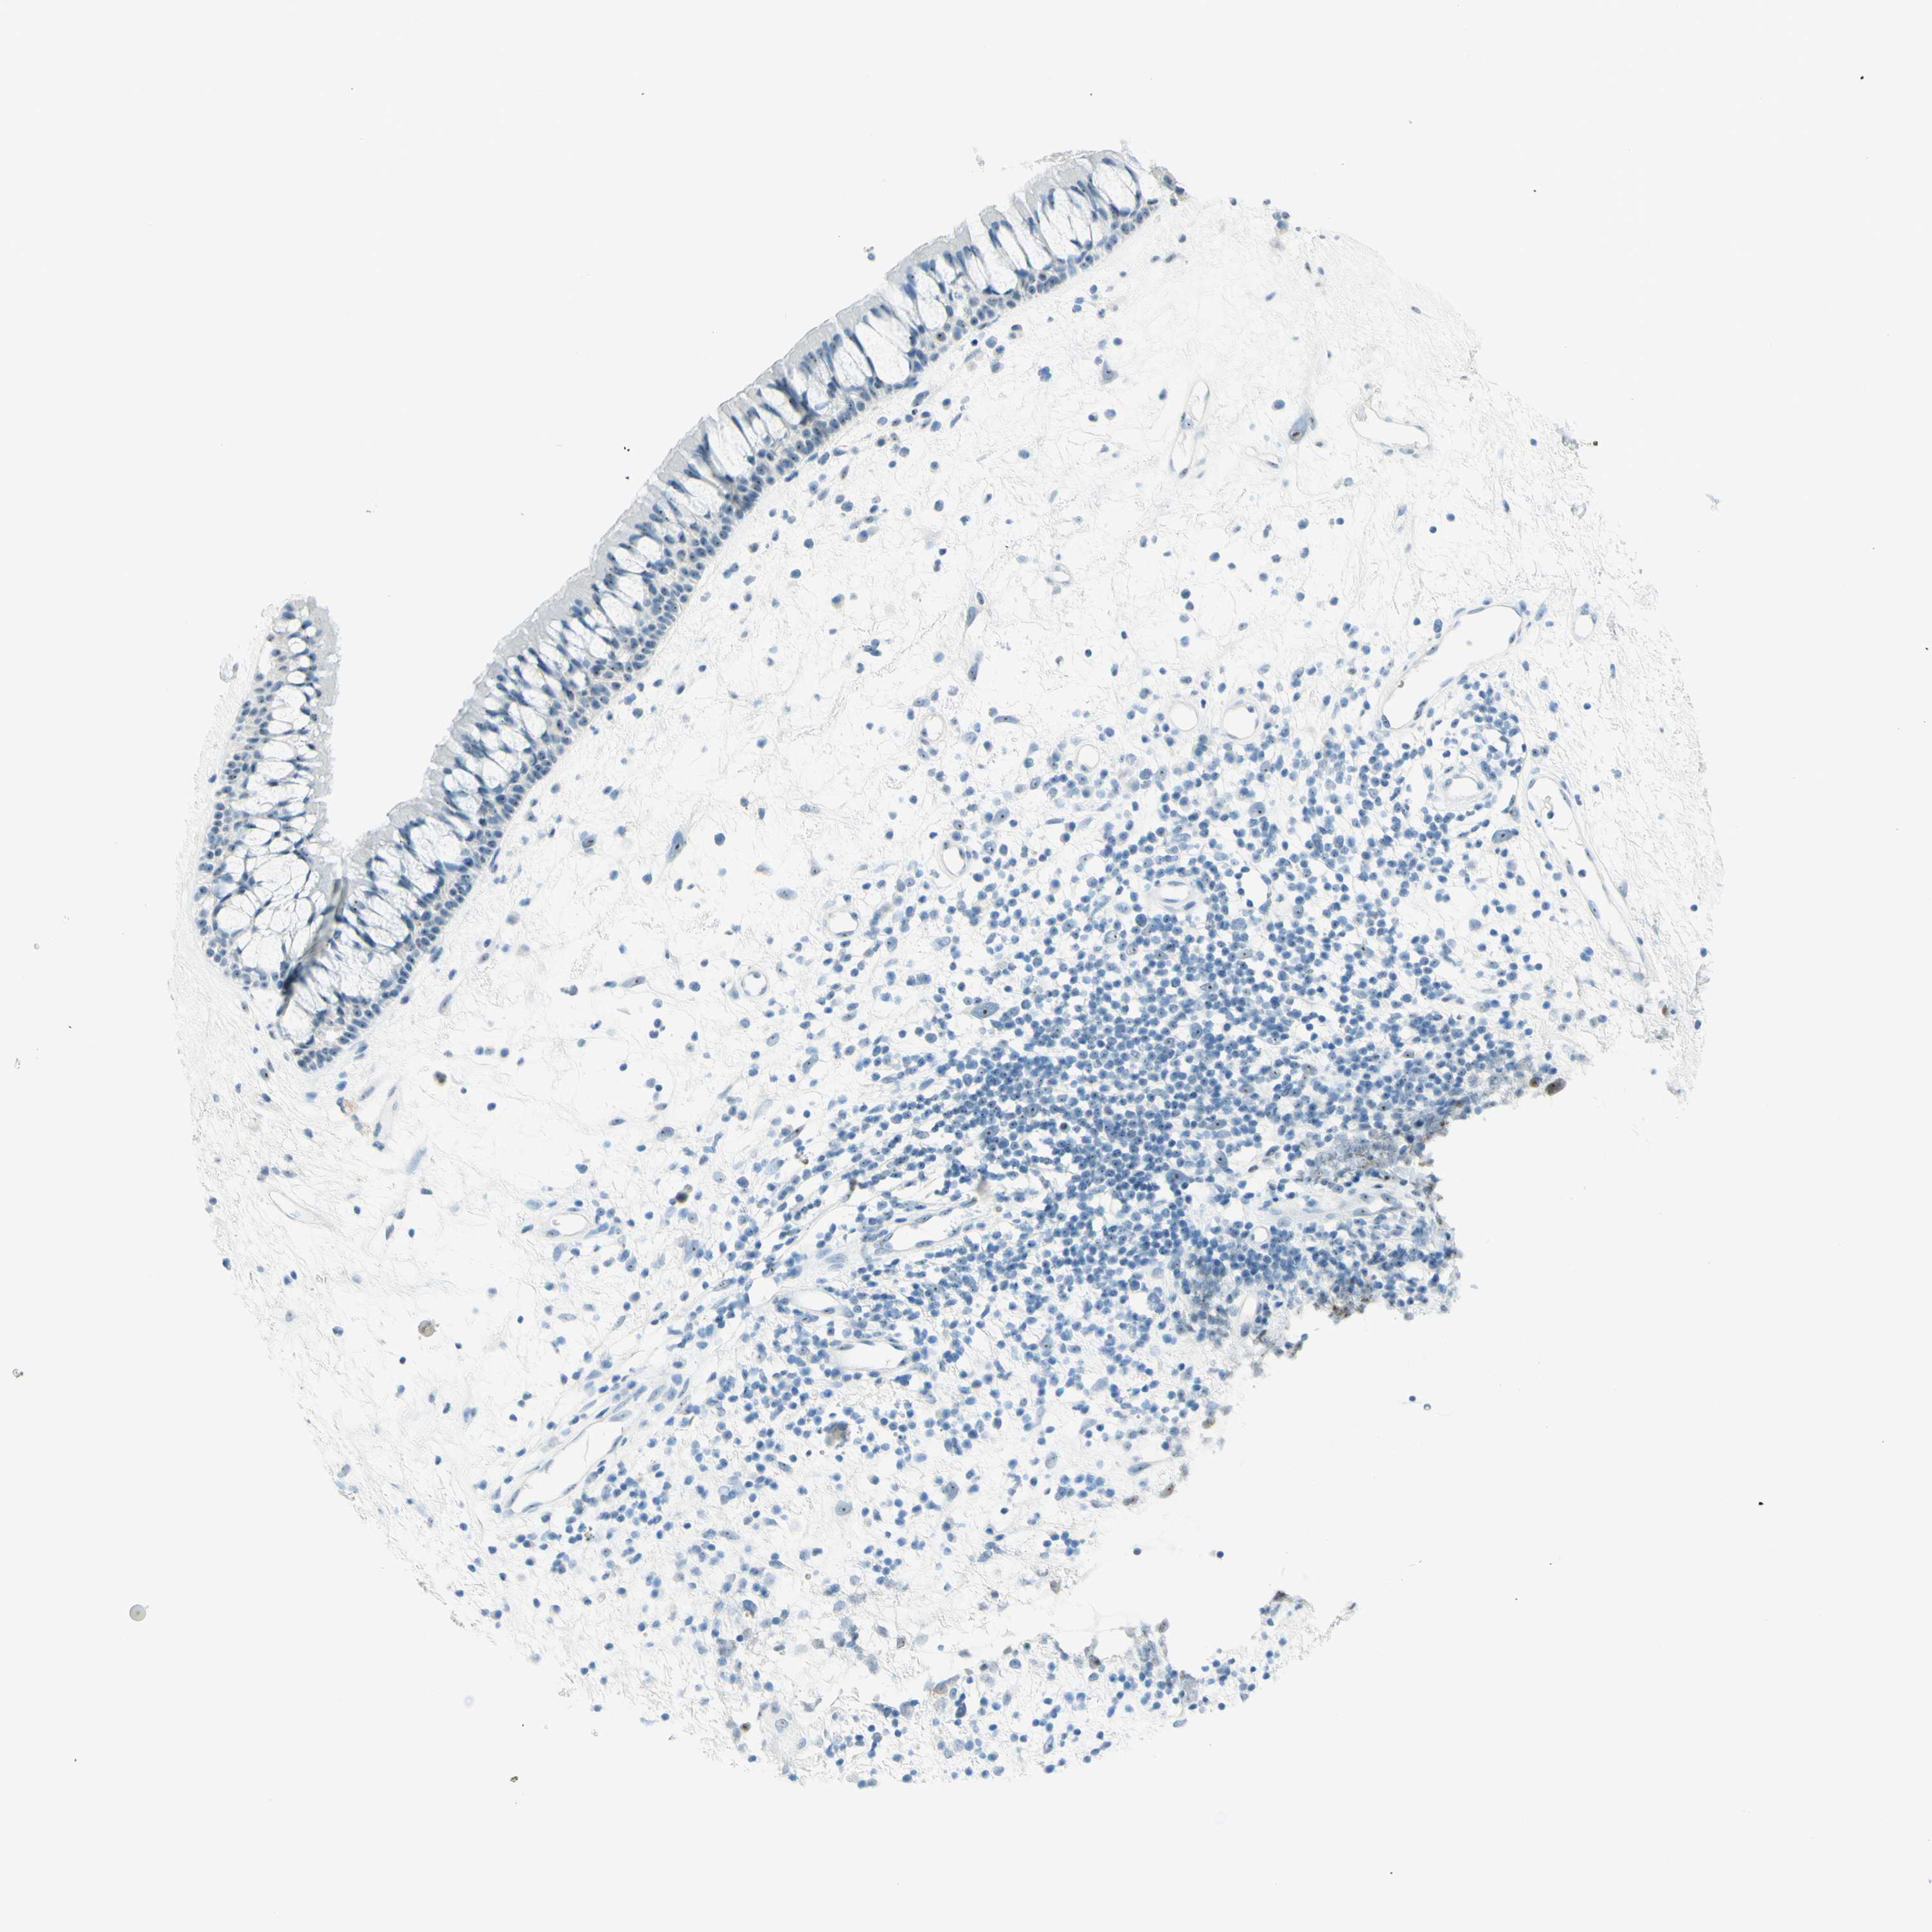

NASOPHARYNX - Antibody stainingi

Antibody staining in the annotated cell types in the current human tissue is reported as not detected, low, medium, or high, based on conventional immunohistochemistry profiling in selected tissues. This score is based on the combination of the staining intensity and fraction of stained cells.

Each image is clickable and will lead to virtual microscopy that enables deeper exploration of all samples and also displays staining intensity scores, fraction scores and subcellular localization as well as patient and tissue information for each sample.

Antibody HPA011284Antibody CAB026403

Respiratory epithelial cells LowNot detected